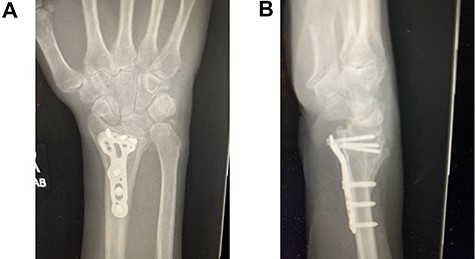

Following appropriate consultation and consent, she underwent total wrist arthroplasty. She reported complete pain relief and an improved range of movement. Ten weeks following surgery the patient presented in the emergency department following a fall. She landed heavily on the dorsiflexed hand and wrist, immediately noticing a change. Imaging confirmed that she had sustained a periprosthetic fracture in the middle finger metacarpal with dorsal displacement of the implant (Fig. 2A and B). Following a trial of non-operative treatment, she underwent revision surgery. The distal metacarpal implant was removed and replaced with a longer implant and the metacarpal fracture defect region was reinforced with autologous bone graft (Fig. 3A and B).

(A and B) PA and lateral radiographs following revision surgery to a longer metacarpal implant.

Three months following surgical treatment of her periprosthetic fracture, when reviewed in the outpatient clinic, the fracture had united and she demonstrated an excellent range of pain free motion and improved wrist function reflected in an improved PRWHE score from 66 preoperatively to 22, 3 months after surgery.